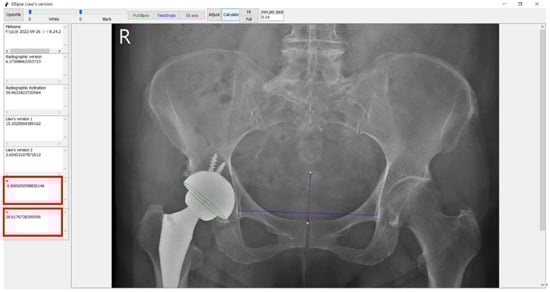

2.5. Software

Yeh, K.-L.; Wu, T.-Y.; Fuh, C.-S.; Chen, C.-S.; Hou, S.-M.; Chiang, C.-H.; Liaw, C.-K. Degree of Pelvic Rotation in the Coronal Plane on Postoperative Radiographs Obtained after Total Hip Arthroplasty. J. Clin. Med. 2022, 11, 6353. https://doi.org/10.3390/jcm11216353